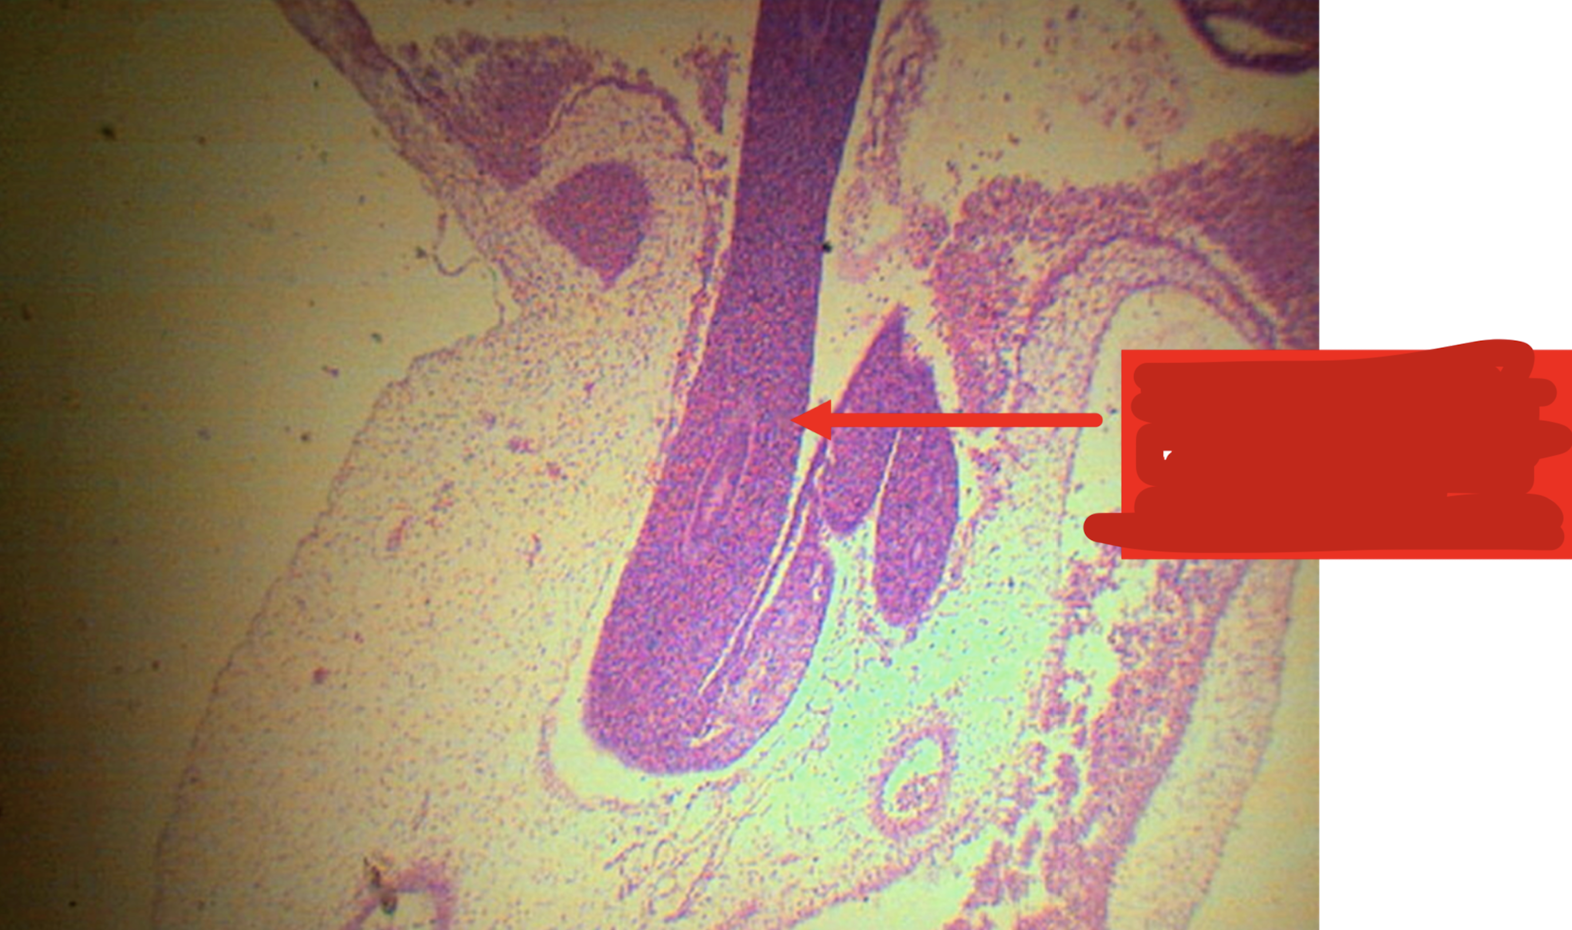

Recto-anal junction

A: rectum (simple columnar with goblet cells)

B: anus (stratified squamous non-cornified epithelium)

Identify the structure

rectum

Goblet cells are most numerous in this segment of the large intestine

rectoanal junction

simple columnar rectum to stratified squamous non-cornified anus